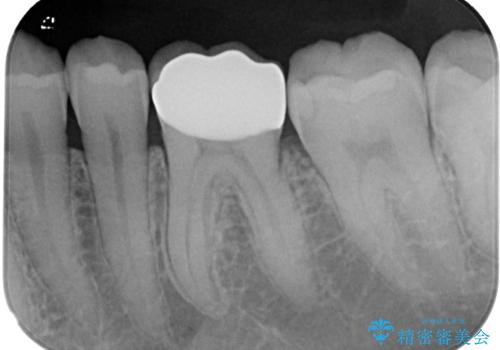

拡大鏡視野下でセラミックインレー、虫歯の除去を行い、オールセラミッククラウンに適した形に整えました。

型どりはシリコーンゴムを用いて精密印象を行っています。

機能面、見た目共に満足していただきました。今後はメンテナンスで通っていただく予定です。